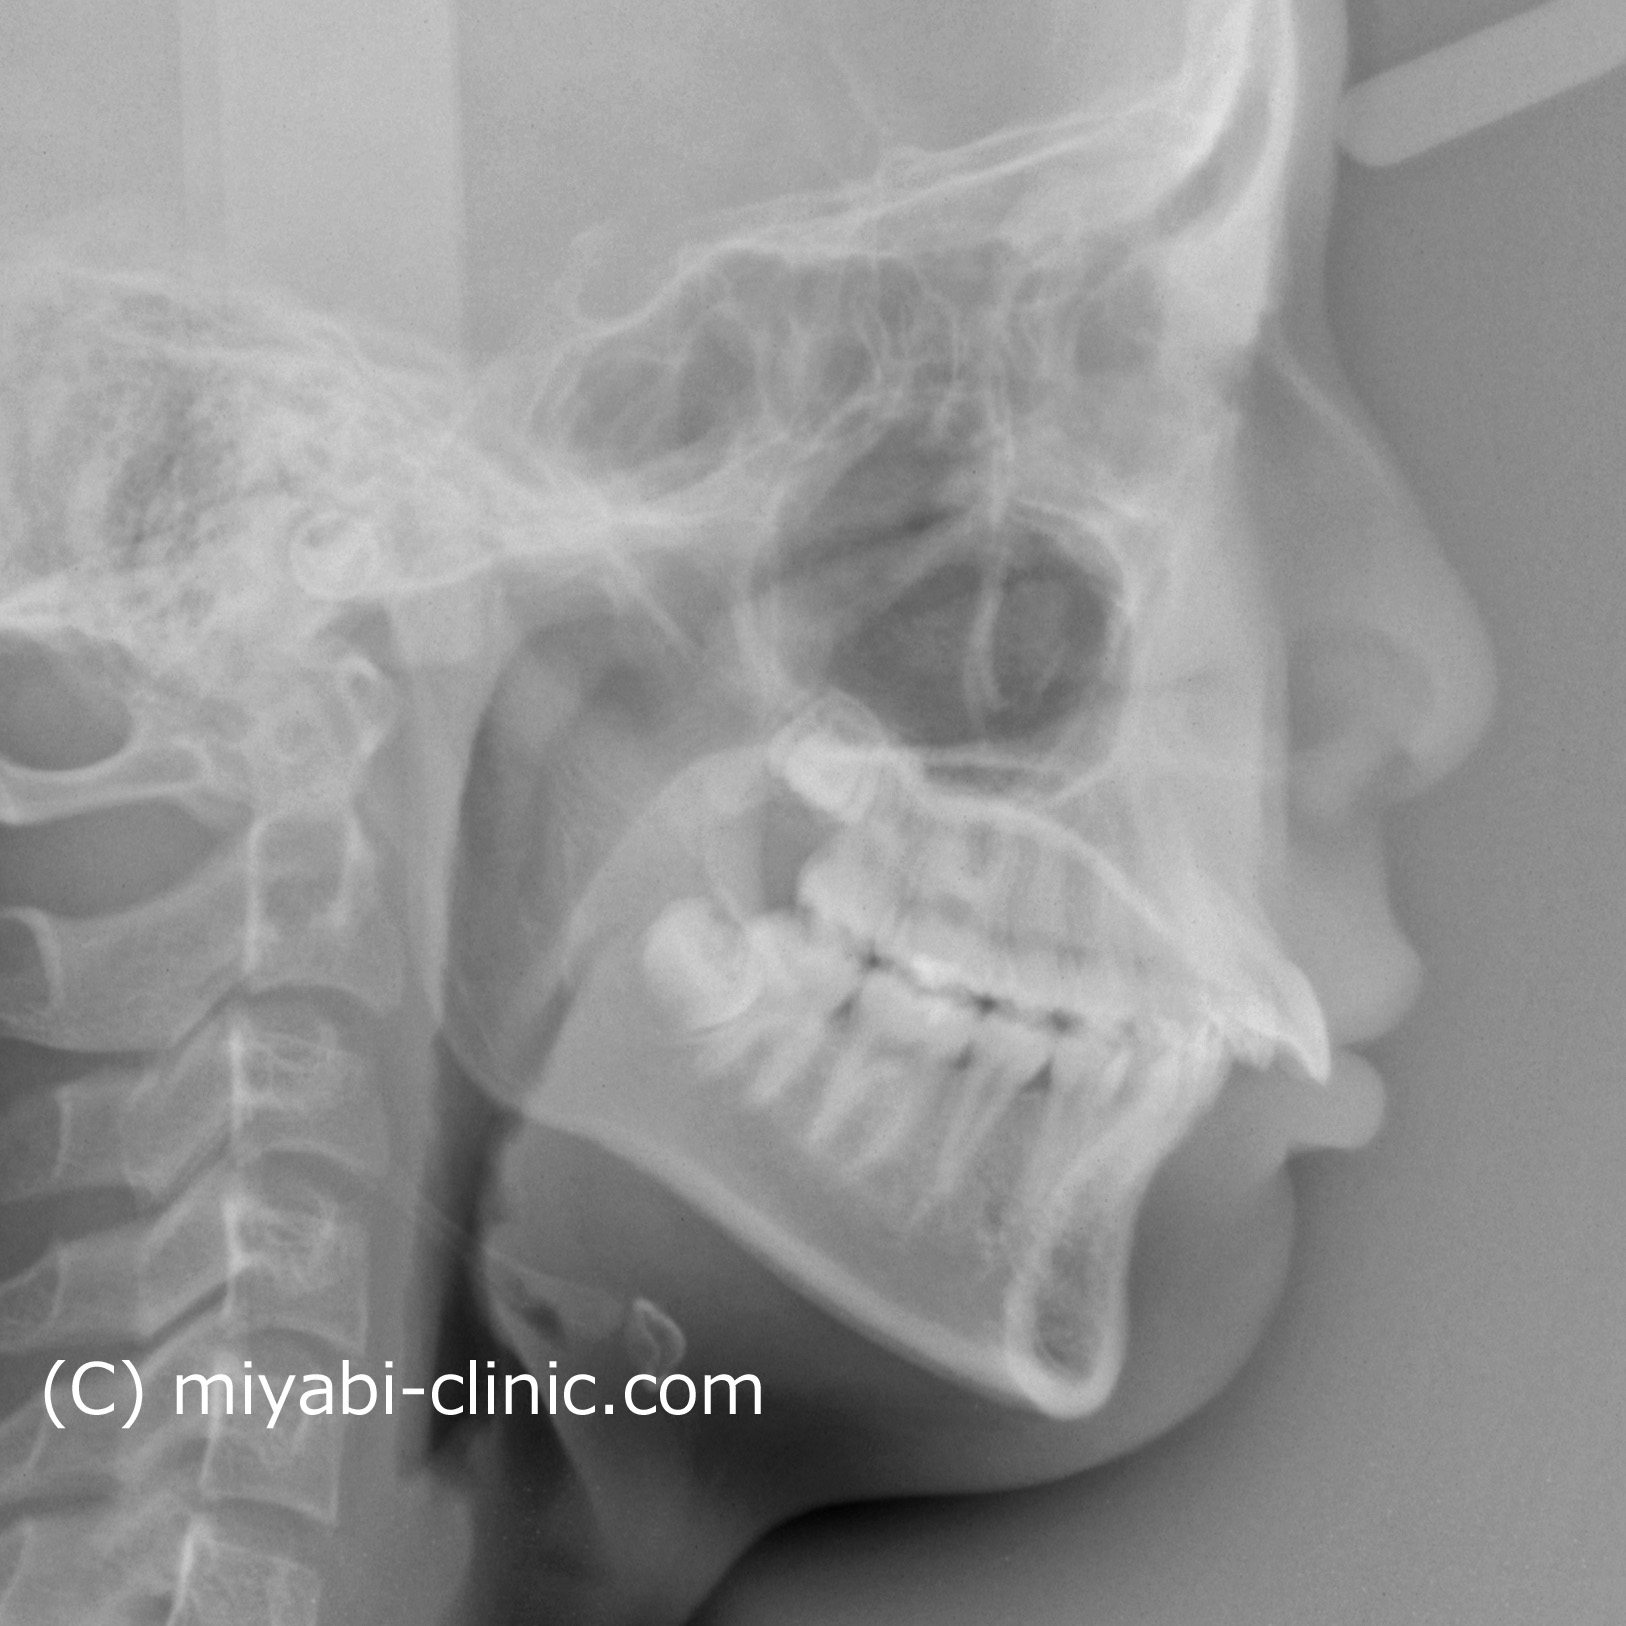

新着情報 1668 治療前セファロ側面 Tweet 投稿日 : 2025年10月19日(日)カテゴリー : コメントを残す コメントをキャンセルメールアドレスが公開されることはありません。 * が付いている欄は必須項目ですコメント 名前 * メール * サイト 14歳 女性「 出っ歯、口もとを 治してほしい」治療期間21か月(上顎前突症) ≫